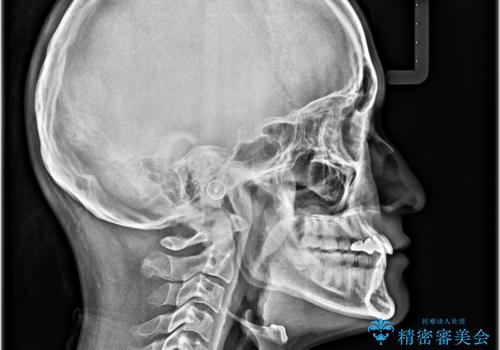

- 上下の前歯のデコボコを改善したいと来院された患者様です。

上顎の歯列幅が狭く、それによって歯が並ぶスペースが不足しています。

また下顎の歯列幅も制限され、内側に歯が倒れています。

それらを改善するため上顎に拡大装置を用いて、審美装置にてワイヤー矯正を行いました。

上顎が側方に拡大されて歯が並ぶスペースを確保できました。

それに伴い下顎の歯列も拡大され、舌側に倒れているのが改善されました。